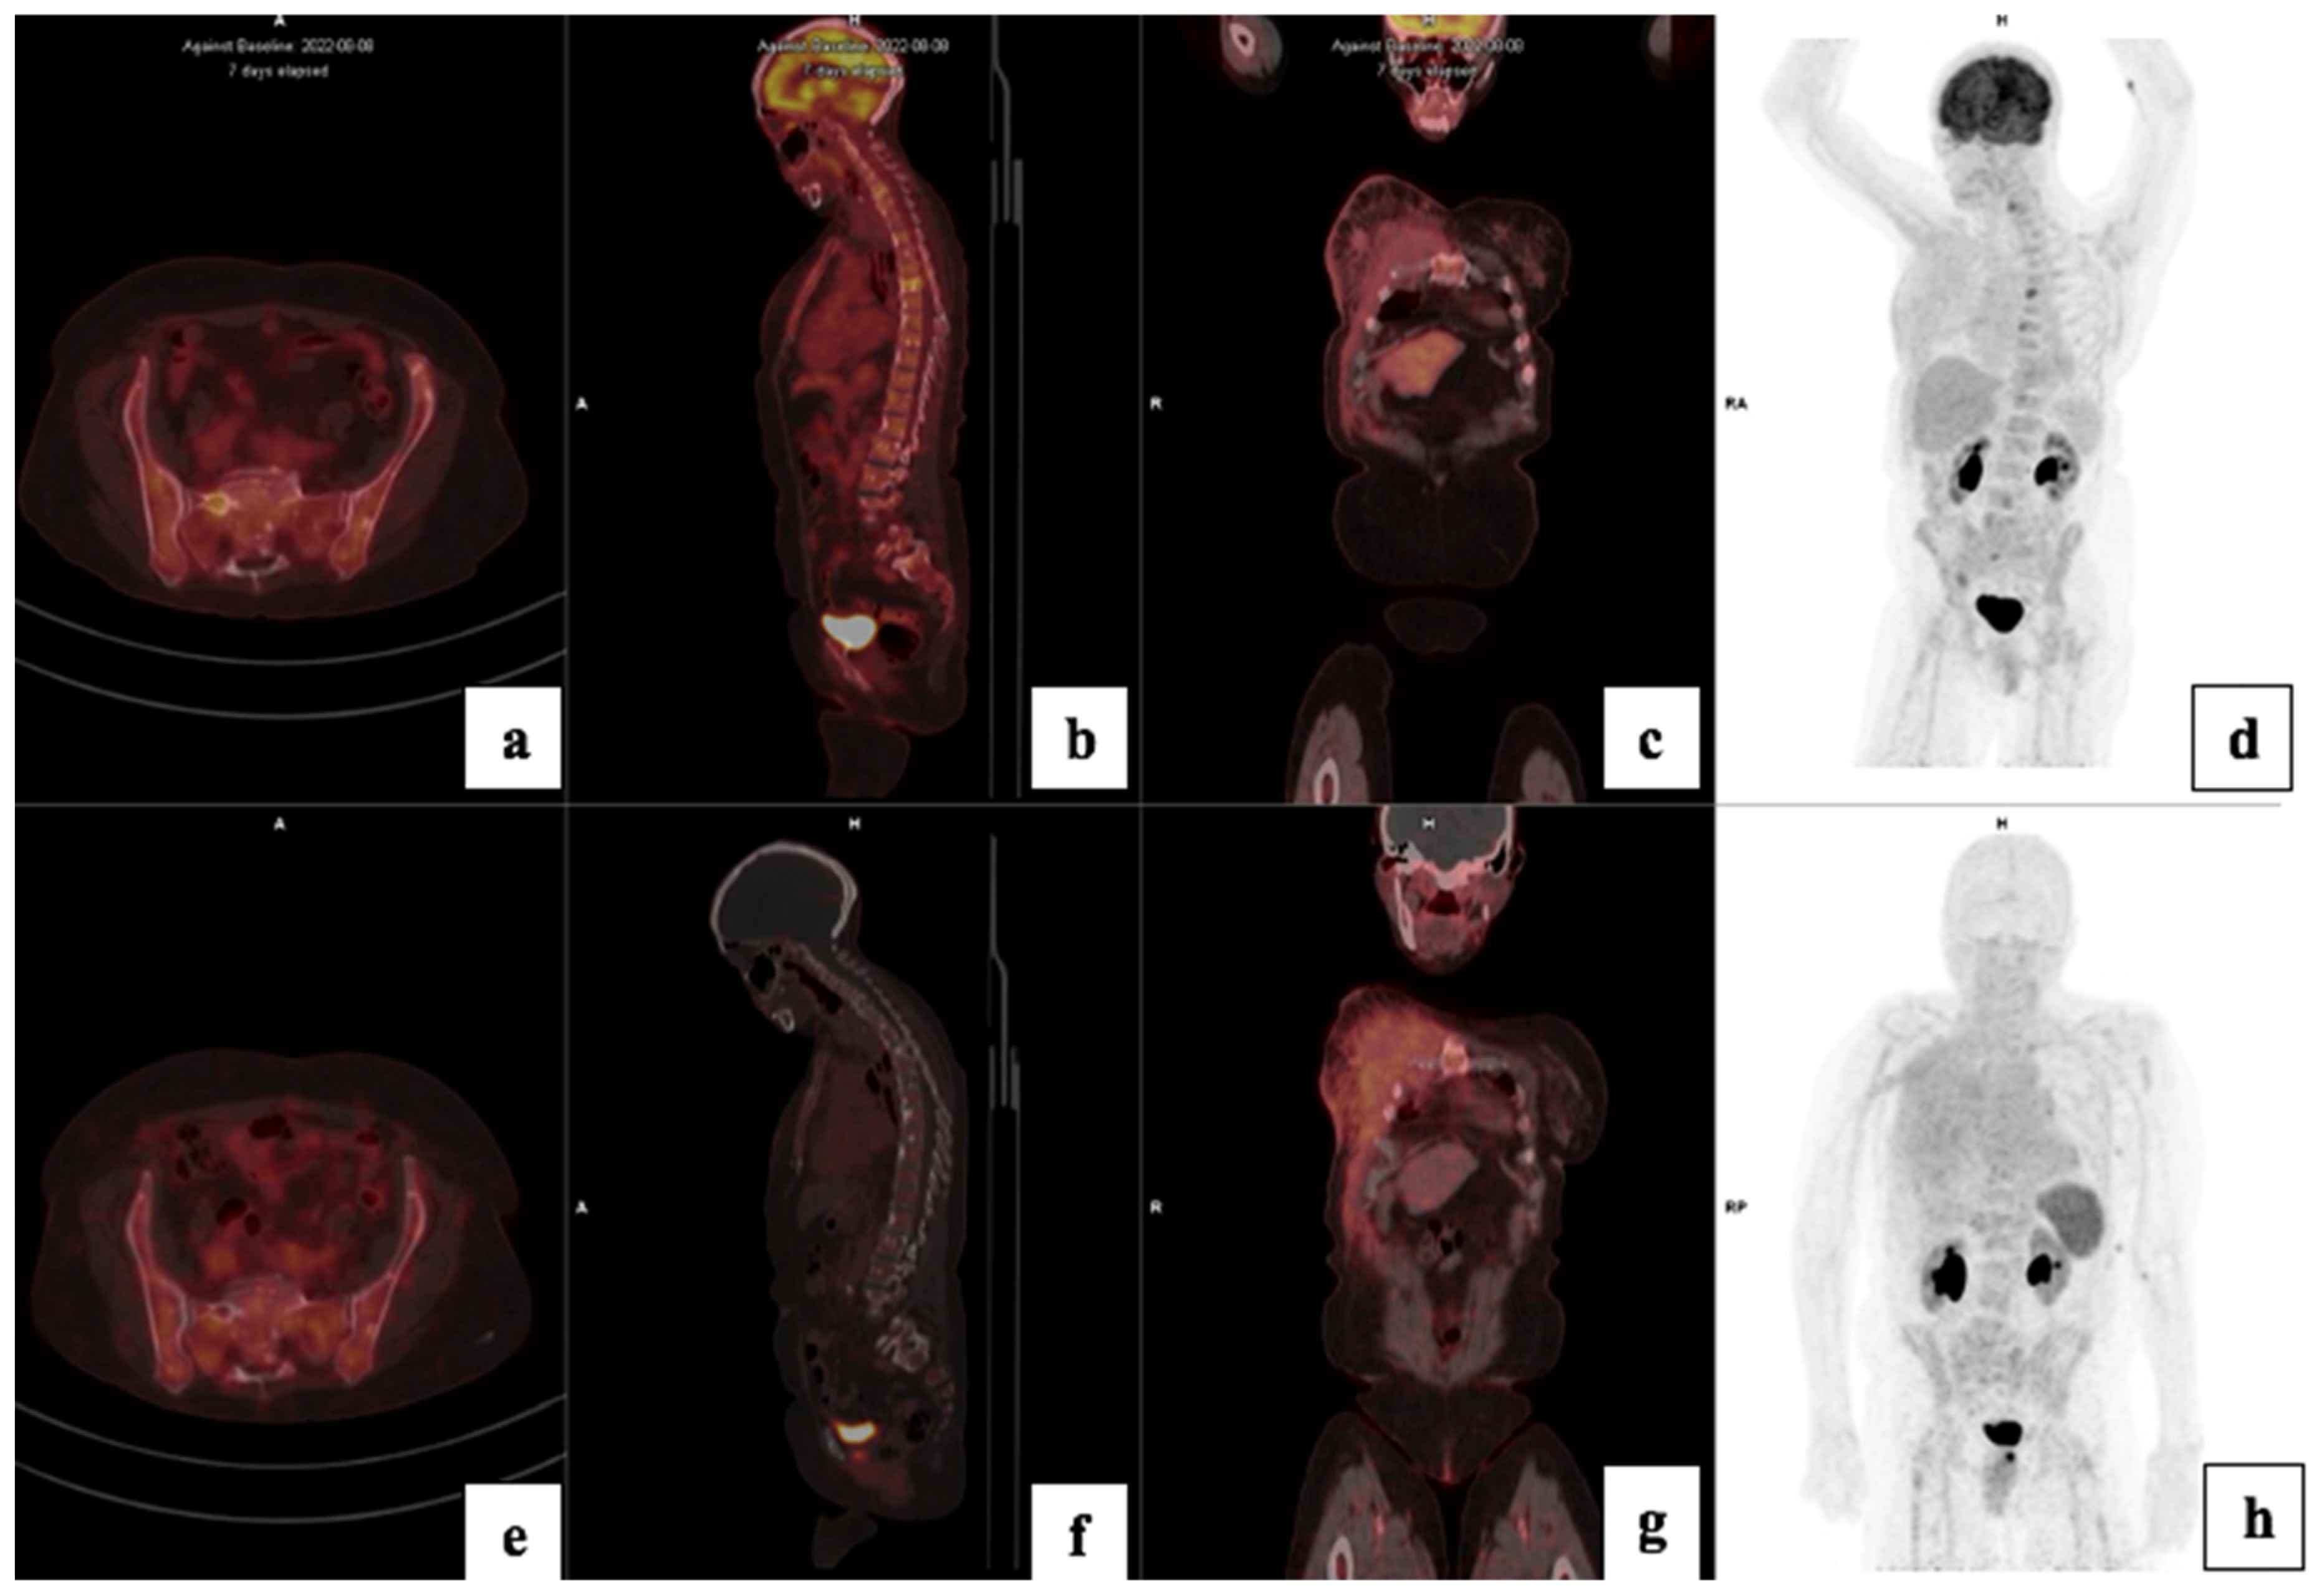

3.4. Visual Analysis

3.5. Treatment Response